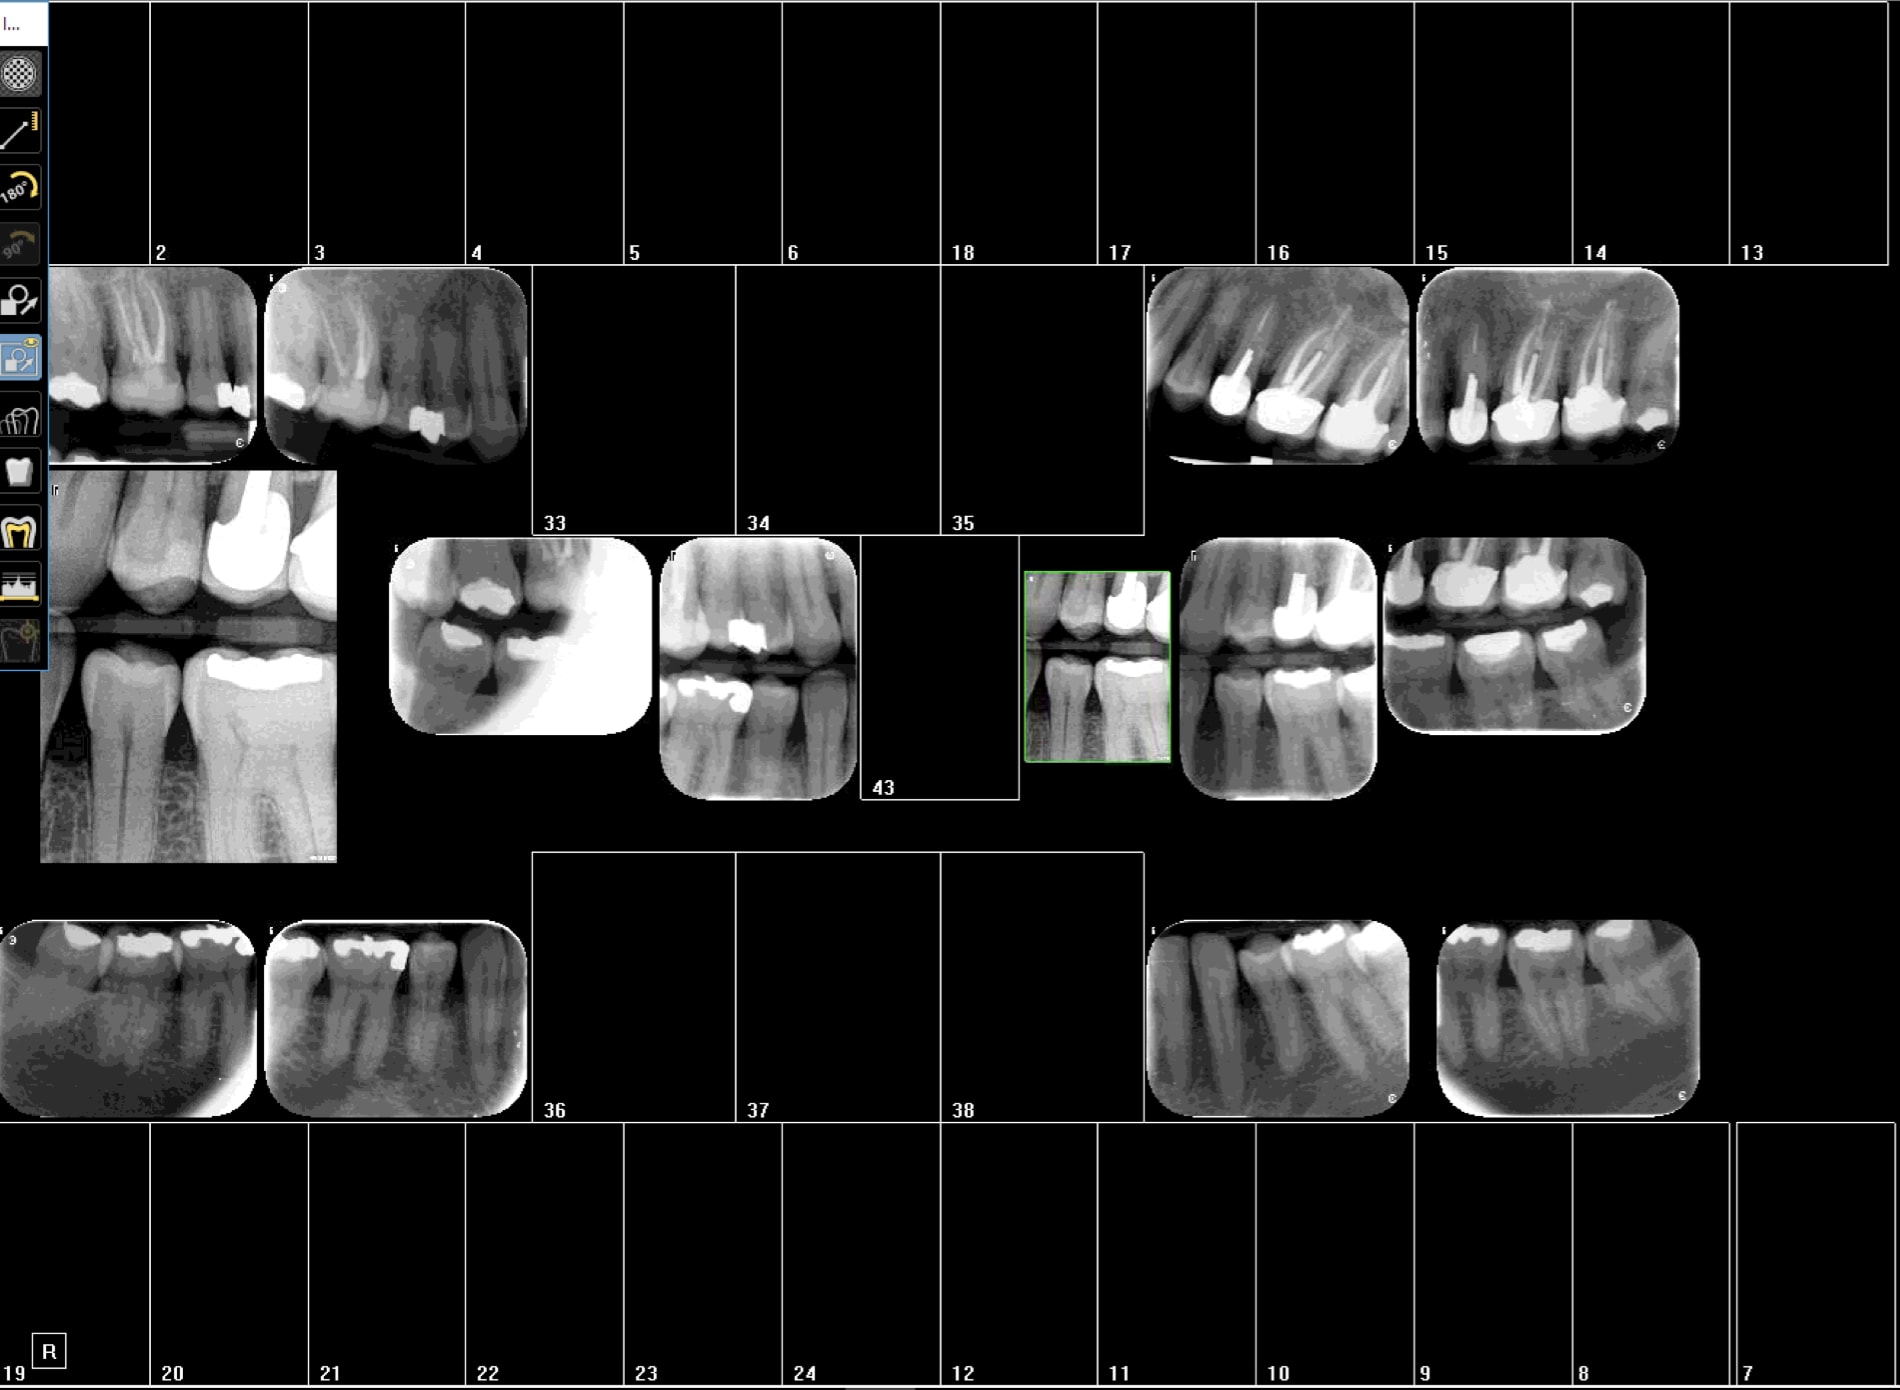

une image RVG versus vistascan neuf

j'ai même zoomé la RVG pour avoir les mêmes tailles

je dirais égalité et contraste supérieur en RVG entre le noir et le gris